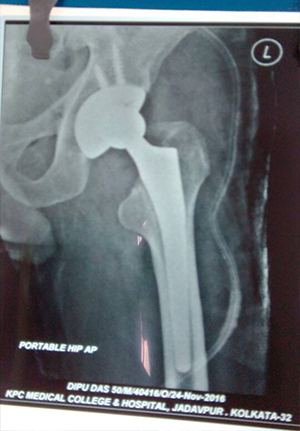

Bipolar hip prosthesis for fracture neck of femure in elder population

primary total hip replacement in ankylosing hip

Complex primary total hip replacment after failed internal fixation